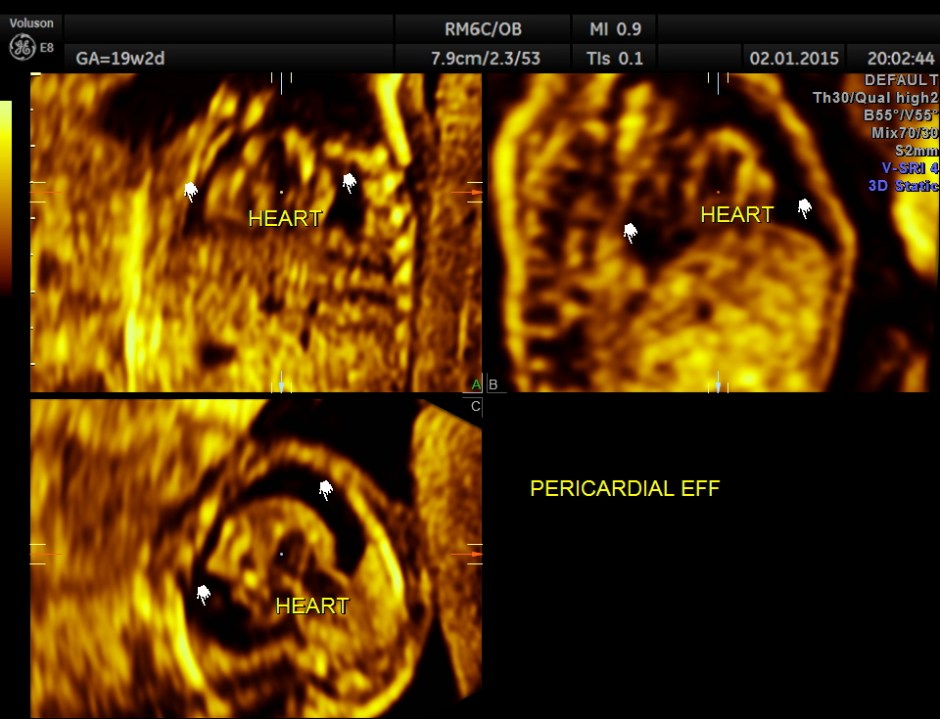

A large pericardial effusion is seen.

This fetus had a large pericardial effusion with structural defect of the heart – VSD and disproportionately smaller left heart – possibly co-arctation of aorta . The patient was advised chromosomal studies and was lost for follow up.